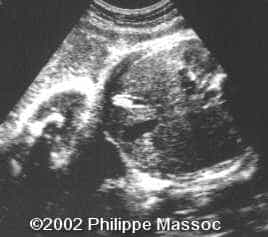

33-year-old, G2P1, no remarkable personal or familial history, with previous normal ultrasound examination at 34 and 37 weeks. During a routine US examination performed at 41 weeks, a hyperechoic structure with a posterior acoustic shadow was observed inside the fetal gallbladder measuring 10.5 x 7.0 mm diameter with regular and flat borders. No other associated anomalies could be seen. (Figure 1). Spontaneous normal vaginal delivery occurred at 41 weeks. The 2-month-old infant is developing normally.

1

There was no evidence of neither ABO nor Rh (D) incompatibility, nor sepsis or other pathology. Two days after birth, an abdominal sonography was performed, confirming the finding of a normal sized gallbladder with thin walls, containing a 9 mm diameter gallstone with posterior acoustic shadow, in the neck. (Figure 2).